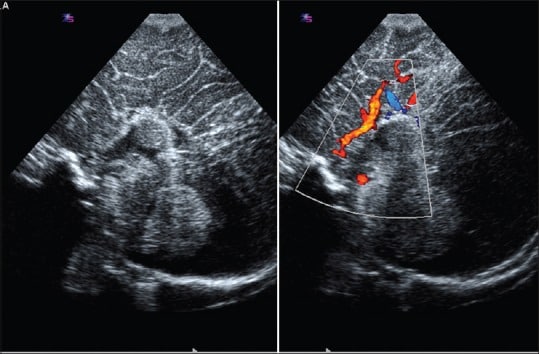

Além disso, utiliza-se imagens com Doppler colorido e espectral para avaliar estruturas vasculares, como o círculo de Willis e a veia de Galeno.

Nos casos de agenesia do corpo caloso, a artéria cerebral anterior pode apresentar um padrão característico, descrito como “sunburst”, visível com precisão nos exames em escala de cinza e Doppler.